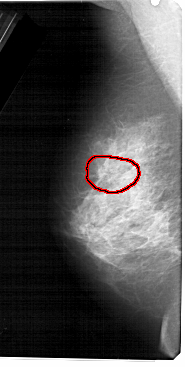

A_1474_1.LEFT_MLO

FILE: A_1474_1.LEFT_MLO.OVERLAY

TOTAL_ABNORMALITIES 1

ABNORMALITY 1

LESION_TYPE CALCIFICATION TYPE PLEOMORPHIC DISTRIBUTION CLUSTERED

ASSESSMENT 4

SUBTLETY 2

PATHOLOGY BENIGN

TOTAL_OUTLINES 2